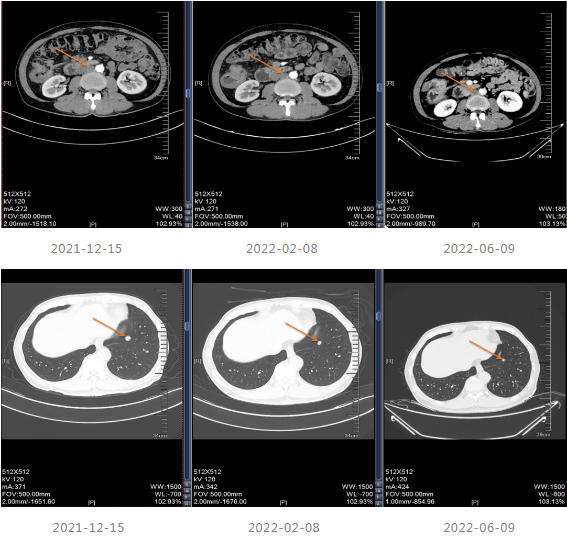

2021-12-15影像学复查提示疾病进展。

▌三线治疗

2021-12-20至2022-03-21更改化疗方案,采用“贝伐单抗+FOLFOX6方案”进行治疗。

2022-04至2022-07采用“贝伐珠单抗联合卡培他滨”维持治疗4周期,维持治疗期间患者渐感腹胀伴消瘦。